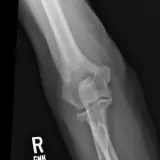

Over 2,100 interactive radiology cases, curated by radiologists for your level of training. Scroll, window, and view cases full screen โ€” just like on PACS. Click linked findings in each writeup to jump straight to them on the image. Cases include sample reports, a focused discussion section, original illustrations, and videos.

Casi completamente interattivi con gli strumenti che ti aspetti su un PACS: scroll, windowing, zoom, pan, misurazioni, ROI e modalitร  a schermo intero.

Annotazioni dettagliate evidenziano i reperti chiave direttamente sui casi. Clicca sui reperti collegati nella descrizione del caso per saltare alla loro esatta posizione sullo scan.